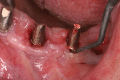

Peri-implant inflammations represent serious diseases after dental implant treatment, which affect both the surrounding hard and soft tissue. Due to prevalence rates up to 56%, peri-implantitis can lead to the loss of the implant without multilateral prevention and therapy concepts. Specific continuous check-ups with evaluation and elimination of risk factors (e.g. smoking, systemic diseases and periodontitis) are effective precautions. In addition to aspects of osseointegration, type and structure of the implant surface are of importance. For the treatment of peri-implant disease various conservative and surgical approaches are available. Mucositis and moderate forms of peri-implantitis can obviously be treated effectively using conservative methods. These include the utilization of different manual ablations, laser-supported systems as well as photodynamic therapy, which may be extended by local or systemic antibiotics. It is possible to regain osseointegration. In cases with advanced peri-implantitis surgical therapies are more effective than conservative approaches. Depending on the configuration of the defects, resective surgery can be carried out for elimination of peri-implant lesions, whereas regenerative therapies may be applicable for defect filling. The cumulative interceptive supportive therapy (CIST) protocol serves as guidance for the treatment of the peri-implantitis. The aim of this review is to provide an overview about current data and to give advices regarding diagnosis, prevention and treatment of peri-implant disease for practitioners.